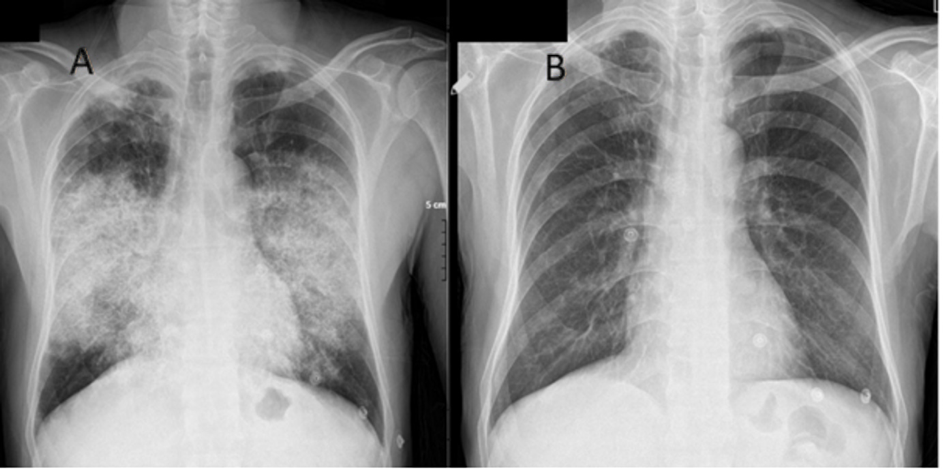

Figure

2:

Chest X-ray (PA view) at presentation (A) and after 8 weeks (B)

days in intensive care. (Figure 2b, Figure 3).